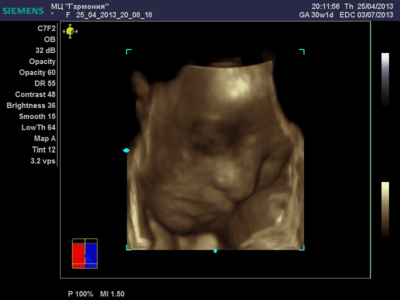

А я вчера на 3Д УЗИ ходила. Моя звезда закрывалась в еми 4мя конечностями. Просто пополам сложилась и спала себе сладко. УЗИстка провела со мной час, кое-как расшевелили маленькую, но ручка была постоянно на мордашке и засыпала она почти сразу снова. Я и на мяче прыгала и живот трясла. В конце более-менее фото вышли, но качество меня не порадовало. Возможно фри оф чардж еще раз переделают. Со средней фотки были отличного качества, а эти сплошное разочарование. Вот тут что-то более-менее еще. Главное пальчик оттопырила так смешно, мол минуточку. Вообще немного жутковатые фотки..хаха

image.jpg [ 47.86 КБ | Просмотров: 1240 ]

Еще одна, качество ужасное..

image.jpg [ 60.32 КБ | Просмотров: 1237 ]

ANGEL*ina, у вас качество очень даже неплохое. GE машины очень хорошие. У моей врачихи такая. Мы сегодня ездили на повторное 3Д узи. Повезло немного больше чем неделю назад. У малыша явно шило в попе. Он кувыркался. За 20 минут несколько раз поменял позицию полностью, и под конец вообще отвернулся. Корд тоже постоянно перед его личиком болтался, да и руками он себя частенько закрывал. Качество фотографий ужасней не придумать.

Вот, пожалуй, самая лучшая фотография.

katerina73 писал(а): Вот, пожалуй, самая лучшая фотография. Катюш, так ваш пупсик зато отлично виден, черты лица отменно видны. Те первые две вчерашние, вторые средней дочки. Со средней черты отлично видны, с этой куклой не понятно..